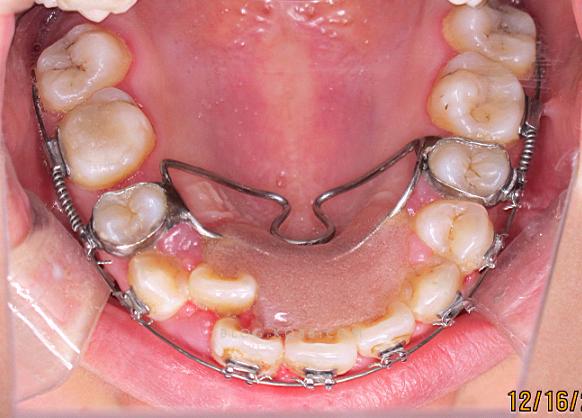

具体过程可分为五个阶段:首先是术前评估,包括口内检查(记录磨牙关系、拥挤度)、模型分析(测量牙弓长度、间隙)、X线片(全景片观察牙根位置,头颅侧位片测量SNA、SNB等指标),结合患者面型、诉求制定个性化方案,其次是支抗装置准备,选择支抗方式,如种植支抗钉(植入上颌颧牙槽嵴或下颌外斜线,提供稳定支抗)或传统支抗(如Nance弓、腭杆,利用后牙支抗),然后是磨牙后推实施,常用技术包括镍钛推簧技术(在磨牙与前牙间放置镍钛推簧,产生持续远中推力)、种植钉辅助技术(种植钉与磨牙间用结扎丝或弹性牵引,直接施加远中力)、摆式矫治器(利用特殊弹簧装置同时远中移动多个磨牙),每4-6周复诊加力,观察磨牙移动速度(理想0.5-1mm/月),磨牙到位后,进入间隙利用与后续矫治阶段:利用获得的间隙排齐前牙(更换细圆丝配合滑动法关闭间隙),调整咬合关系(如尖牙关系、颌间牵引),最后是保持阶段:拆除矫治器后,佩戴保持器(如Hawley保持器、透明保持器),至少12-24小时/天,预防复发。

| 摆式矫治器 | 利用杠杆原理同时移动多颗磨牙 | 同时移动多颗牙,效率高 | 装置复杂,口腔舒适度低 | 双侧磨牙需同时后推 | 5-8 |